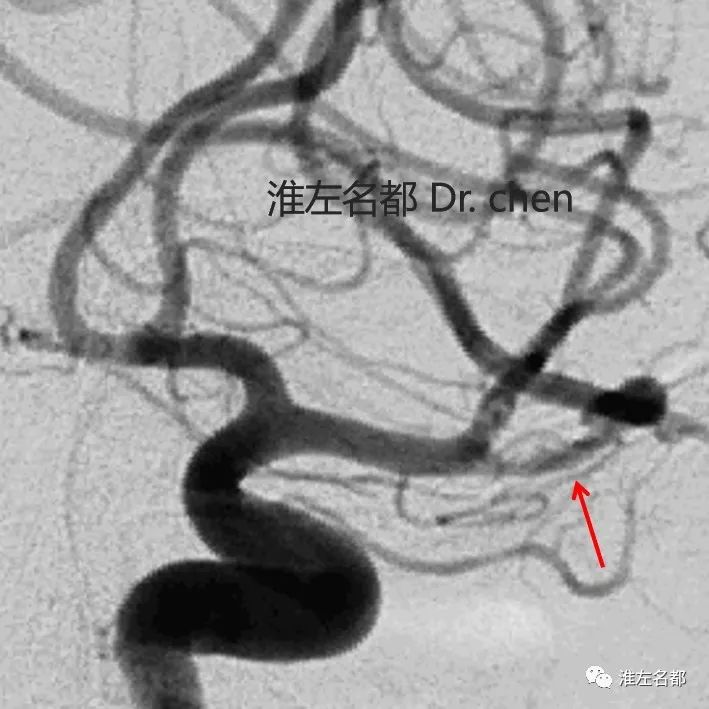

△左侧颈动脉三维DSA:左侧大脑中动脉上干局部狭窄

(橙箭),左侧大脑中动脉下干局部囊状扩张(红箭)。

△左侧颈动脉三维DSA及其血管断面重建图像:

左侧大脑中动脉上干局部内膜征(橙箭)。